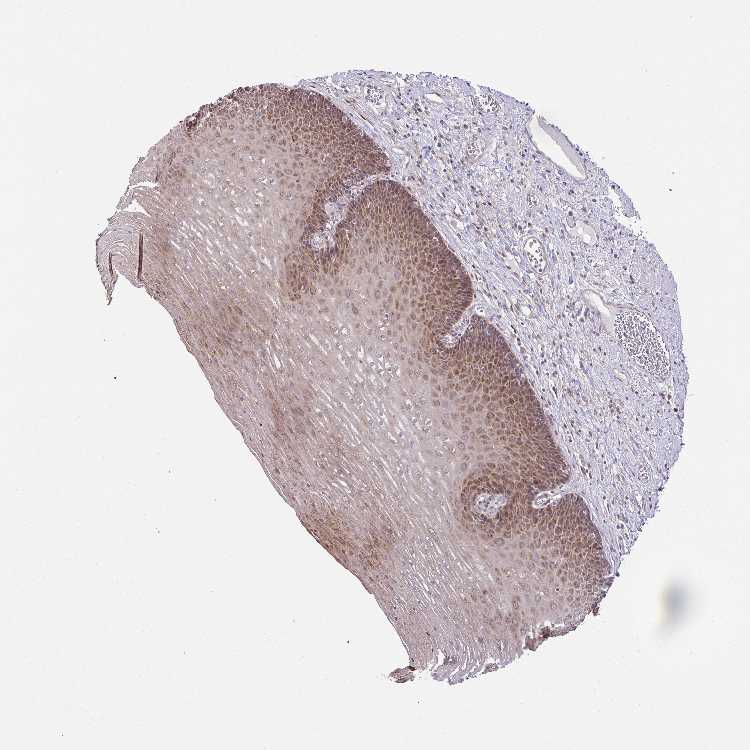

ESOPHAGUS - Antibody stainingi

Antibody staining in the annotated cell types in the current human tissue is reported as not detected, low, medium, or high, based on conventional immunohistochemistry profiling in selected tissues. This score is based on the combination of the staining intensity and fraction of stained cells.

Each image is clickable and will lead to virtual microscopy that enables deeper exploration of all samples and also displays staining intensity scores, fraction scores and subcellular localization as well as patient and tissue information for each sample.

Antibody HPA056686

Squamous epithelial cells High